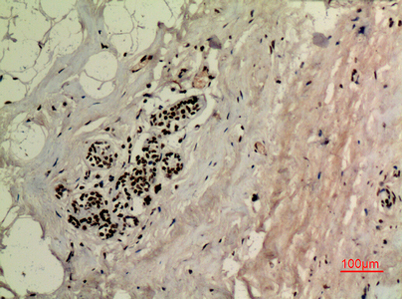

Product name: p53 (Acetyl Lys370) rabbit pAb

Dilutions: Western Blot: 1/500 - 1/2000. IHC-p: 1:100-300 ELISA: 1/20000. Not yet tested in other applications.

Immunogen: The antiserum was produced against synthesized Acetyl-peptide derived from human p53 around the Acetylation site of Lys370. AA range:331-380